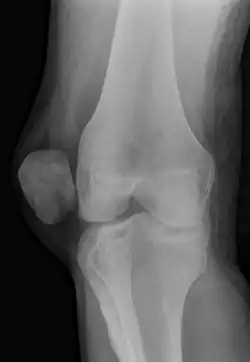

On X-ray, with skyline projections, dislocations are readily diagnosed. In borderline cases of subluxation, the following measurements can be helpful:

• The lateral patellofemoral angle, formed by:[16]

• A line connecting the most anterior points of the medial and lateral facets of the trochlea.

• A tangent to the lateral facet of the patella.

With the knee in 20° flexed, this angle should normally open laterally.[16]

• The patellofemoral index is the ratio between the thickness of the medial joint space and the lateral joint space (L). With the knee 20° flexed, it should measure 1.6 or less.[16]